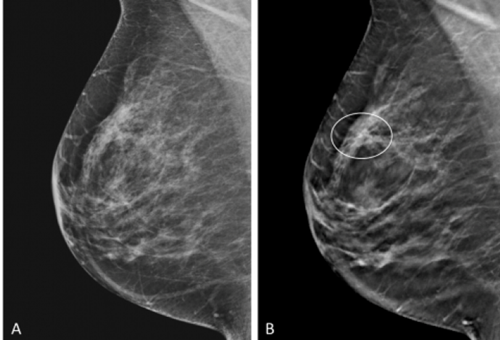

目前乳腺攝影檢查是公認(rèn)的乳腺篩查手段,而,多數(shù)亞洲女性的乳房較致密的,會(huì)影響到乳房攝影的判斷率,所以,并不是攝影說沒事就沒事。當(dāng)要做定期檢查時(shí),大家最怕「這個(gè)檢查不舒服」!讓人打消一年報(bào)到一次的念頭。做乳腺攝影時(shí),技術(shù)師會(huì)用壓克力板夾住患者的乳房,左右夾一次,上下夾一次,被夾過的人常覺得痛得不得了而超有陰影。

因此很多女性并不知道乳房超音波的重要性,乳房超音波是可以用來區(qū)辨腫瘤的用來區(qū)辨乳房里的纖維囊腫與其他實(shí)心腫瘤,如纖維囊腫、良性實(shí)心腫瘤的特征、惡性實(shí)心腫瘤的特征等。

30歲以上就應(yīng)該定期做乳房超聲波檢查。做乳房超音波不會(huì)那么不舒服?;颊咛稍跈z測床上,醫(yī)師會(huì)擠上一些凝膠,拿超音波探頭微微壓迫乳房,并從不同方向滑過,以確保了解每個(gè)位置的乳房狀況。若看到有疑慮的東西,醫(yī)師可操控探頭,從不同的角度切入,用多個(gè)平面的影像得出空間感,了解疾患的型態(tài)。